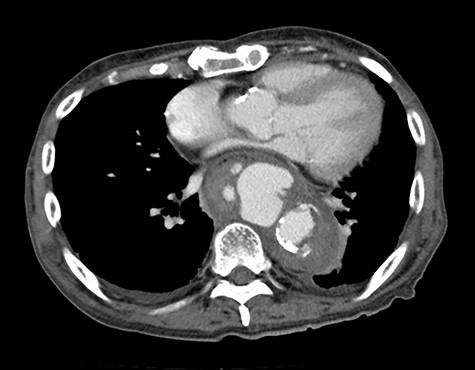

The patient was an 81-year-old man with a history of maintenance dialysis due to diabetic nephropathy, right hemicolectomy due to transverse colon cancer, coronary artery bypass grafting and abdominal aorta-femoral-popliteal bypass surgery due to peripheral arterial disease. The patient complained of anorexia for the last 1 month, and a screening computed tomography (CT) scan revealed a ruptured descending aorta (Fig. 1). He was transferred to our hospital for surgical management. At the time of admission, his vital signs were stable, but blood tests indicated a systemic infection, given that his leukocyte count was 14 510/μl and C-reactive protein was 27.92 mg/dl.

CT at the time of admission shows irregular shape of the aneurysm.